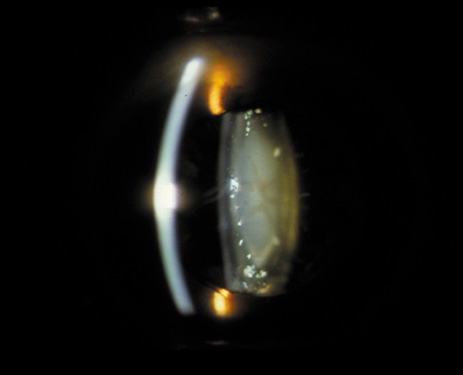

One can examine this type of cataract with direct illumination, using the narrow and broad beams of the slit-lamp to show the characteristic granular inner surface immediately in front of the posterior capsule (Fig. 13). The problem with this technique, however, is that patients may not tolerate any prolonged direct illumination because of the glare. Retroillumination is therefore more useful for revealing the outline of the opacity, since it is usually seen as an “island” in the center of the posterior capsule, which is further highlighted by the shadow cast by the opacities.33 However, in the early stages of this type of cataract, the dust-like particles that might be noticeable in the central posterior subcapsular area with direct illumination disappear or are difficult to see with retroillumination (Fig. 14). Eventually this “dusting” becomes dense enough to cast a shadow and thus appear on retroillumination. The smooth orange background of the fundus helps to highlight the rough, irregular pseudopodia-like edges of the central opacity. In advanced stages, the PSC may become a thick, calcified plaque (Fig. 15). During surgery, excessively vigorous scraping or vacuuming of the calcified opacity can lead to rupture of the posterior capsule. Usually, small remnants that are left behind after surgery are reabsorbed and do not interfere with vision; otherwise, they are easily treated with a neodymium : yttrium (Nd:YAG) aluminum garnet laser. Pathologic evidence suggests that most PSCs result from the migration of bow region cells into the potential space (along with accumulated cellular debris) between the posterior capsule and the cortex.34–36

Fig. 13. Direct slit-lamp illumination of a PSC, showing an irregular granular surface in front of the posterior capsule.